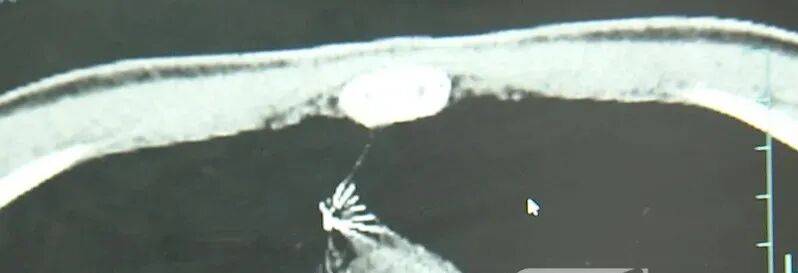

近日,安徽17岁小伙小陆参加征兵体检,胸片结果显示:胸腔内有一处金属高密度影,形态细长,像一根针虚拟货币是什么。

进一步的CT检查确认,异物是一枚金属针,斜插在肺组织内,位置十分凶险虚拟货币是什么。

杭州市第一人民医院心胸外科副主任冯兴说:“我们看到这个针的尖锐部,正好指向他体内的一个大血管,边上是上腔静脉和胸主动脉,因此这个针稍有不慎,就有可能造成周边血管的损伤,甚至危及生命虚拟货币是什么。”